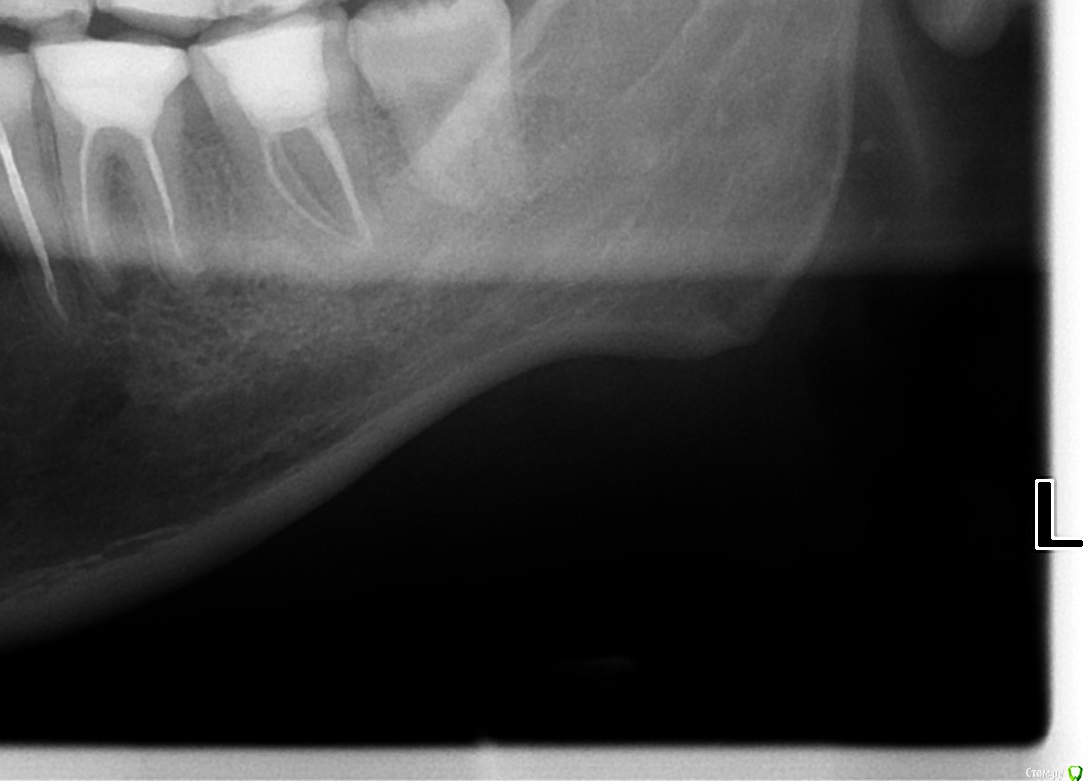

Chef Опубликовано 11 сентября, 2015 Поделиться Опубликовано 11 сентября, 2015 При осмотре у стоматолога (частный кабинет у дома) обнаружился свищ с внешней стороны десны у нижней семерки слева (37 ?), сделали снимки, на нём гранулема или киста у леченого ранее зуба.Из свищевого хода при надавливании выходит гной, а так зуб не как не беспокоит.Она предложила удалить зуб.Да еще и напугала, что при есть вероятность задеть общий нерв и в результате получить онемение части лица (?). Меня как-то всё это смутило... Я пошел в другую клинику проконсультироваться, там сказали, что можно попробовать перелечить проблемный зуб, но гарантии 50/50, что смущает, хотелось бы более уверенный прогноз результата.Там у них нет микроскопа и врача работающего с ним, эдодонтиста, просто терапевт общей практики.Я не решился на лечение у них. Подскажите, можно этот зуб вылечить? Снимки выкладываю. Ссылка на комментарий

St. Опубликовано 11 сентября, 2015 Поделиться Опубликовано 11 сентября, 2015 3.6 и 3.7(второй и третий с конца) перелечить и коронки. 100% гарантии на повторное лечение каналов не бывает в принципе, и вобщем-то микроскоп - штука нужная и полезная, но далеко не панацея. 3 Ссылка на комментарий